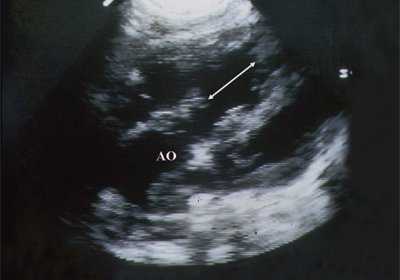

В равной степени это относится к дефекту межжелудочковой перегородки (рис. 6), простой форме транспозиции магистральных сосудов (рис. 7, 8), транспозиции магистральных сосудов с дефектом межжелудочковой перегородки (синдром Тауссиг - Бинга) (рис. 9), общему желудочку (рис. 10), общему артериальному стволу (рис. 10), двойному отхождению сосудов от одного из желудочков сердца (рис. 11).

Рис. 6. Дефект межжелудочковой перегородки. Длинная ось сердца. Стрелками показан дефект межжелудочковой перегородки.

LV и RV - левый и правый желудочек, АР - легочная артерия, АО - аорта, VSD - дефект межжелудочковой перегородки.